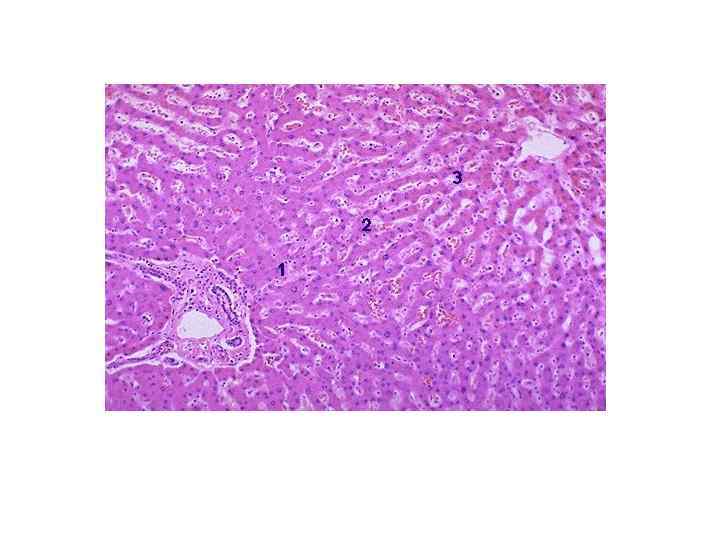

Печеночный ацинус • -Первая зона- (темные гепатоциты) интенсивный метаболизм протеинов и синтез плазменных белков • -Третья зона- (светлые гепатоциты) преобладает обмен липидов и ксенобиотиков • -Вторая зона-промежуточное положение • Зональная гетерогенность -динамическая и функциональная структура как в норме, так и при патологии

ЦИРРОЗ ПЕЧЕНИ МИКРО • -МОНОЛОБУЛЯРНЫЙ- узелок образуется на территории одной дольки, в узле отсутствуют портальный тракты и центральные вены • -МУЛЬТИЛОБУЛЯРНЫЙ- узелки образованы несколькими дольками, портальные тракты и центральные вены есть